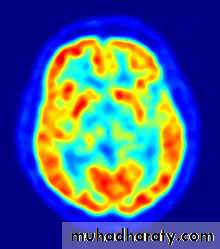

-CT Scan, Ultrasound, MRI, Radionuclide imaging & PET , Basic principles